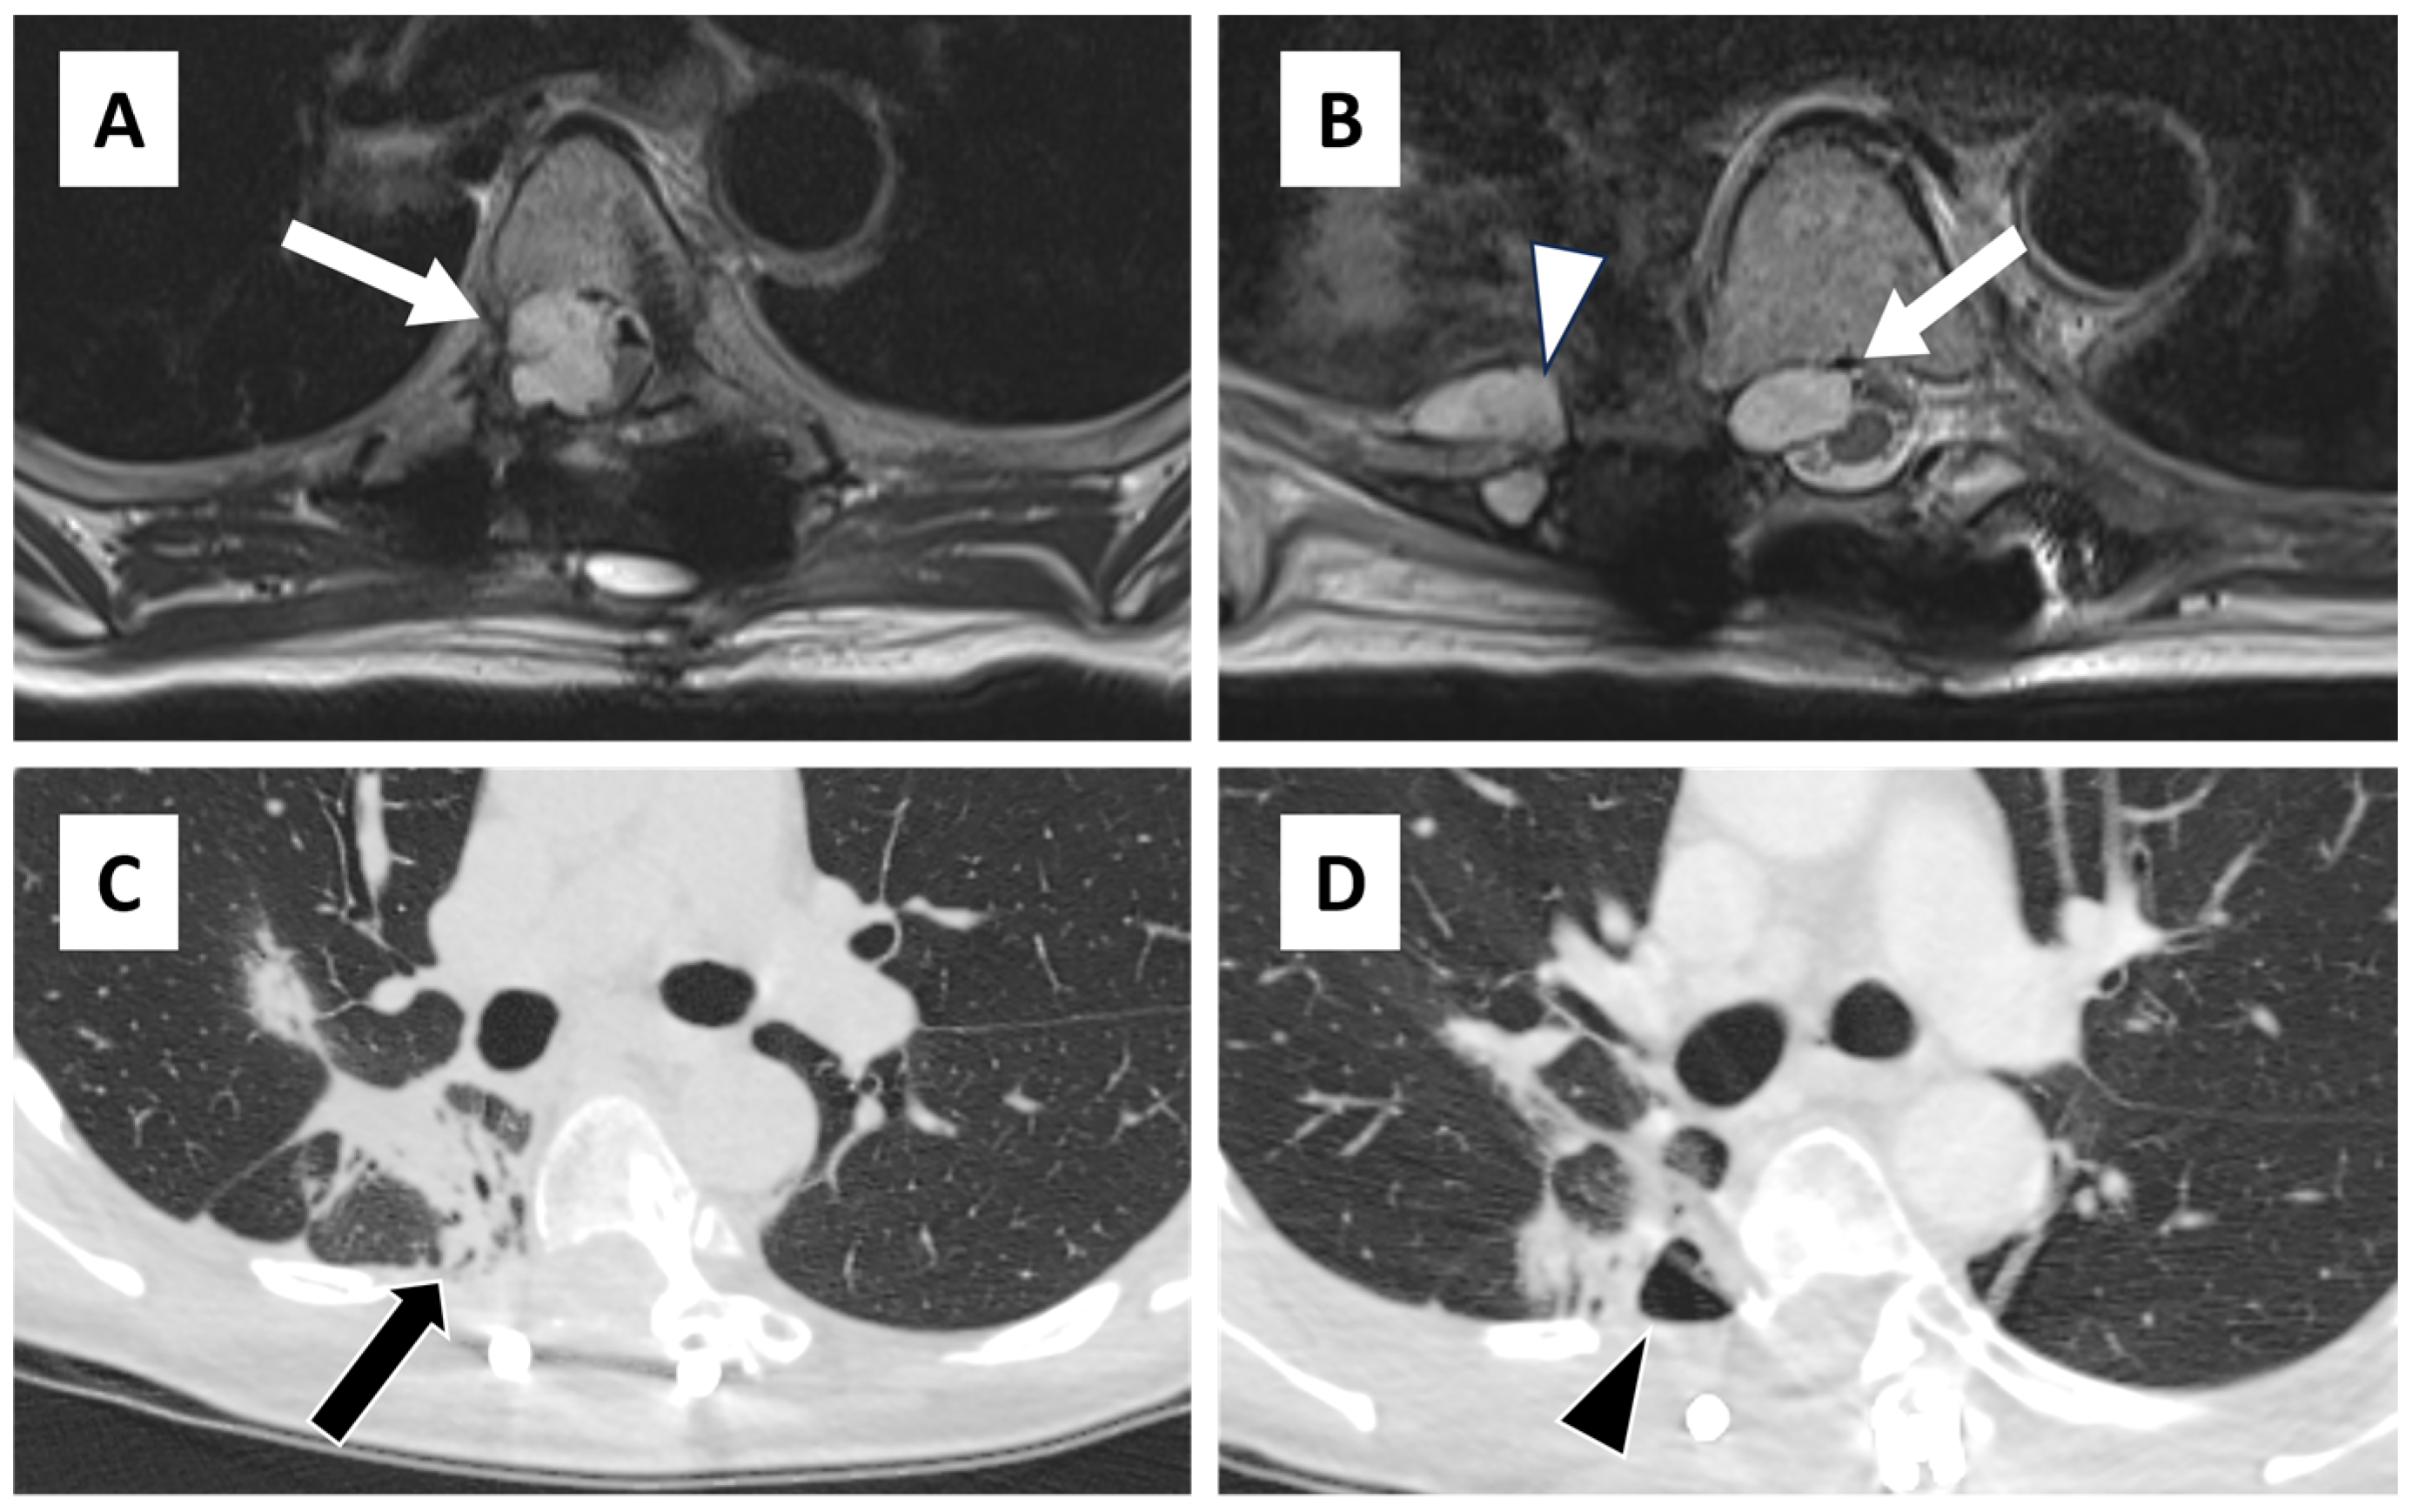

Figure 1. Axial T2-weighted fast spin echo images taken 1 month prior to repeat chondrosarcoma resection demonstrate recurrent T2 hyperintense tumor in the epidural space (arrow) above the prior operative bed (A) as well as within the prior operative bed (B) with additional tumor along the proximal edge of the partially resected right 8th rib (arrowhead). Axial pre-procedural planning CT of the thorax (C) demonstrates post radiation changes in the adjacent lung with focal bronchiectatic consolidation in the medial right lower lobe (arrow) and (D) a small adjacent contained hydropneumothorax (arrowhead). There was no specific evidence of pleural damage during the debulking surgery; however, the procedure was notably challenging due to altered anatomy from prior surgeries and radiation therapy. The patient had a chronic dry cough that did not worsen after surgery, and there was no cerebrospinal fluid expectoration observed. CT scans of her chest consistently showed no other significant pneumothorax or pleural effusion.